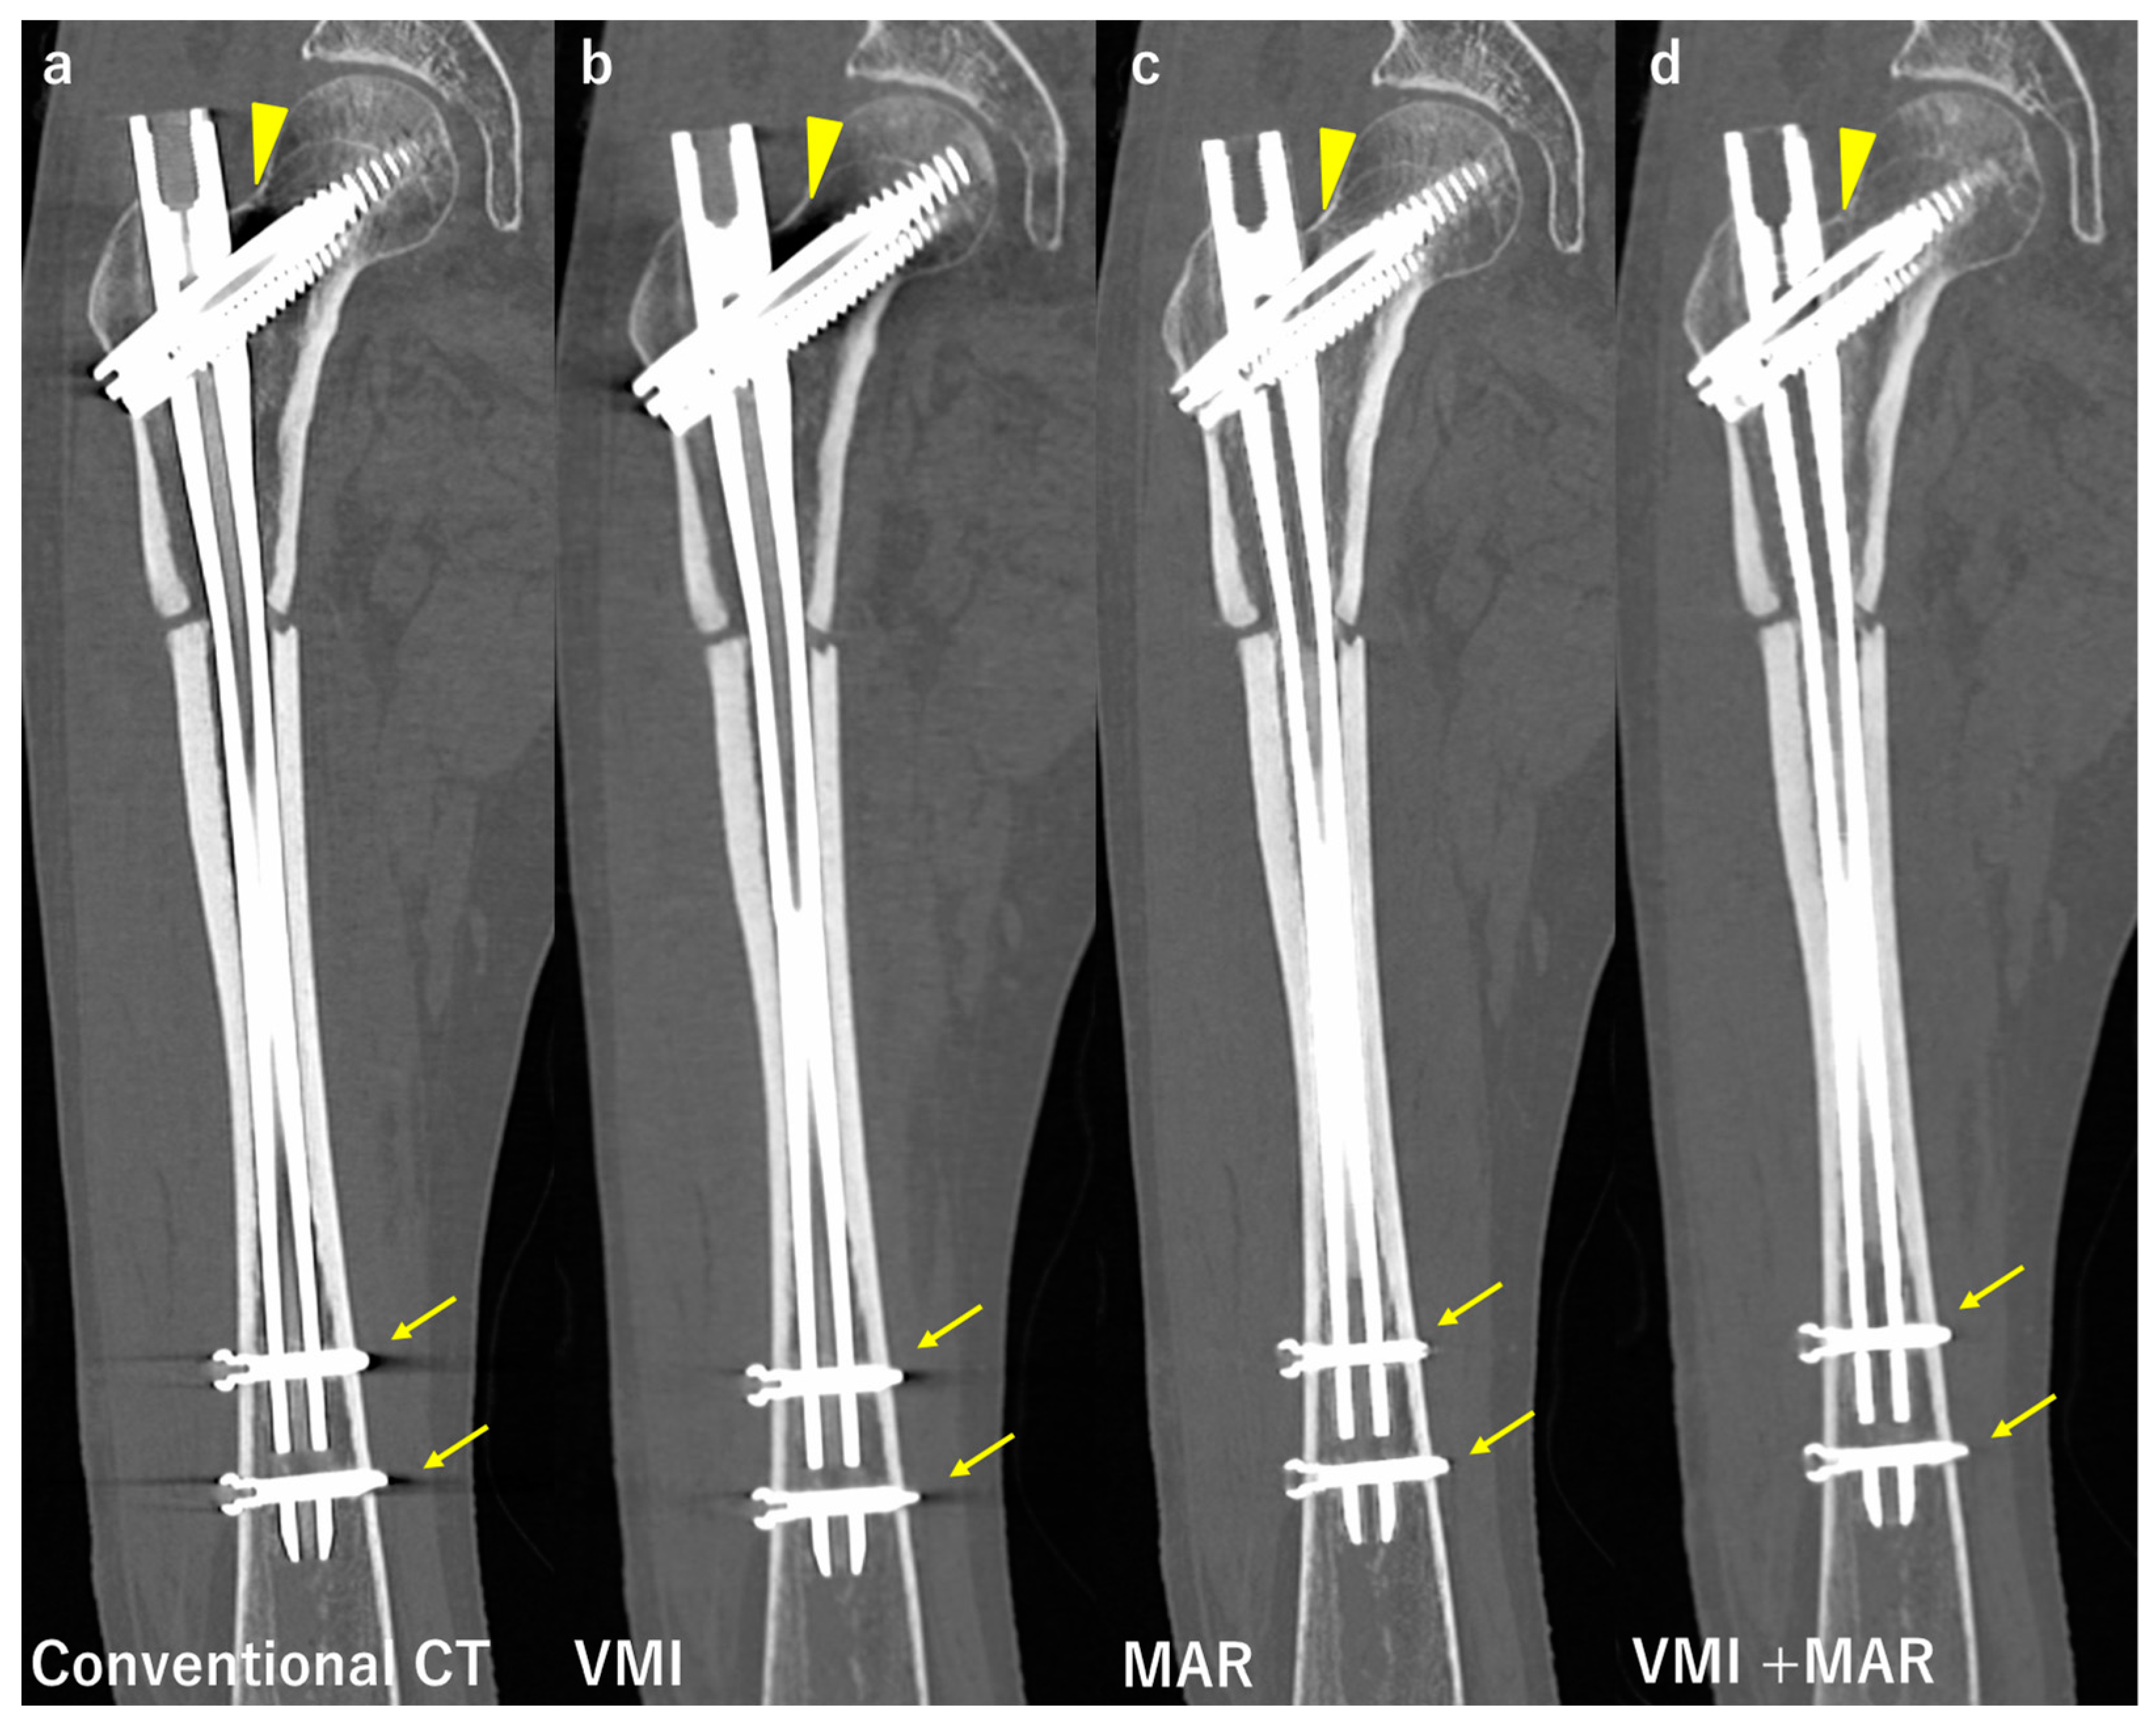

| Neuhaus et al. [42] | Conventional CT, MAR, VMI, VMI + MAR | 24 patients after THA | VMI + MAR reduced artifacts the most. VMI + MAR improved the assessment of adjacent structures the most. |

| Andersson et al. [57] | Conventional CT, MAR, VMI, VMI + MAR | Bilateral hip prosthesis phantom | Artifact reduction rate MAR 52–75% VMI 12–52% (in a certain region artifact increased up to 32%) VMI + MAR 75–77% |

| Bongers et al. [58] | Conventional CT, MAR, VMI, VMI + MAR | Hip prosthesis and dental implants. Qualitative and quantitative evaluation. | Artifact reduction rate (Hip, dental implant, respectively) VMI 33%, 8% MAR 56%, 71% VMI + MAR 76%, 76% |

| Long et al. [59] | MAR VMI VMI + MAR | 20 patients with instrumented spines. Artifact score (1 to 5) Image quality score (1 to 4) | VMI + MAR showed the best artifact and image quality scores. ICC 0.779 |